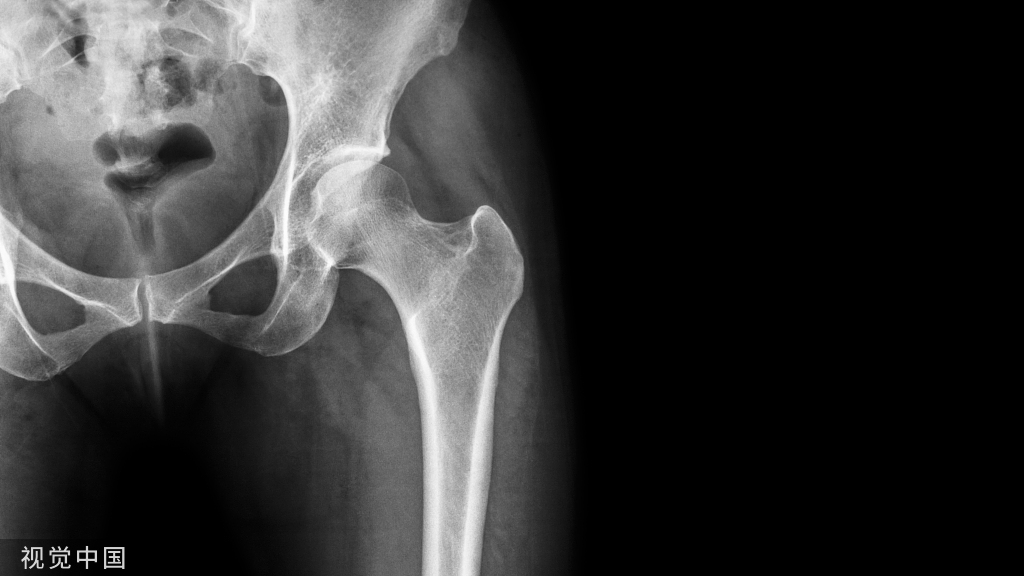

膝盖退化性关节炎,在X光上最明显的变化是软骨流失和骨刺形成,而进行肌骨超声检查,可以发现膝盖周边的韧带肌腱都有受损的状况